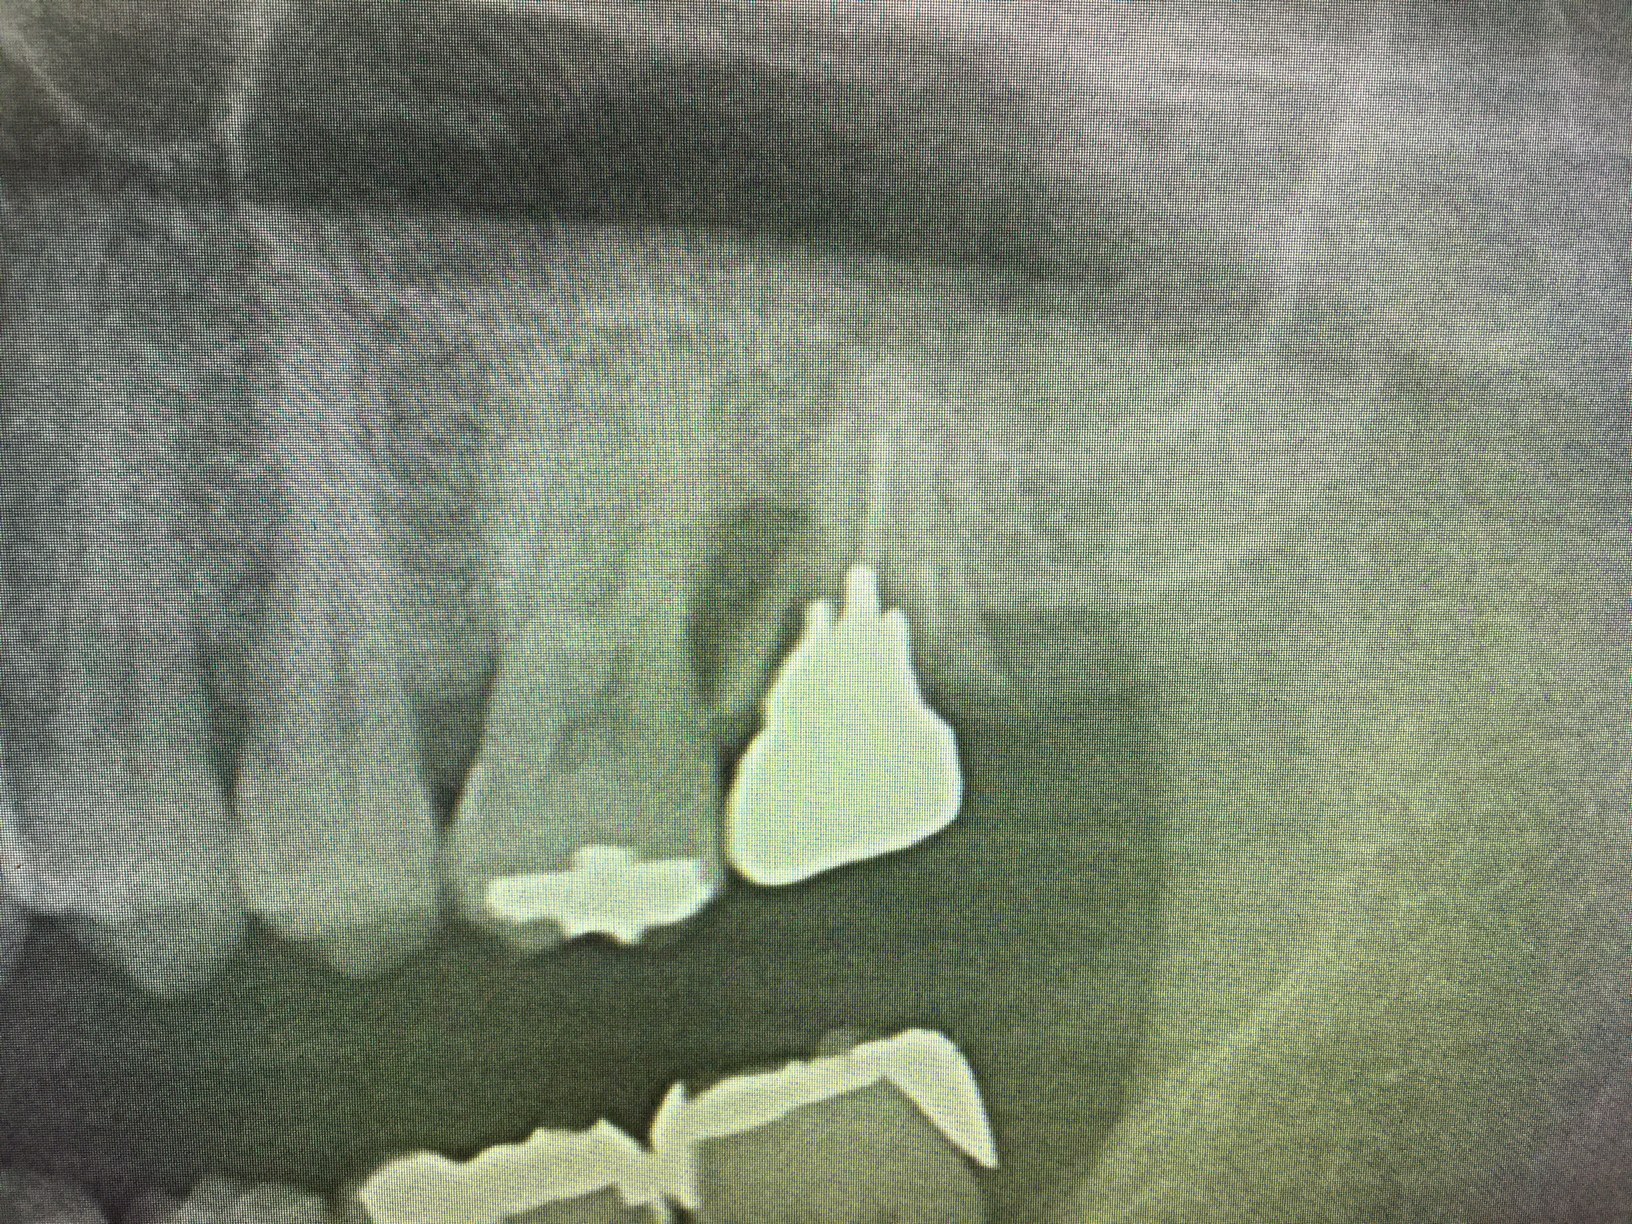

マイクロスコープ(歯科用顕微鏡)の世界とは